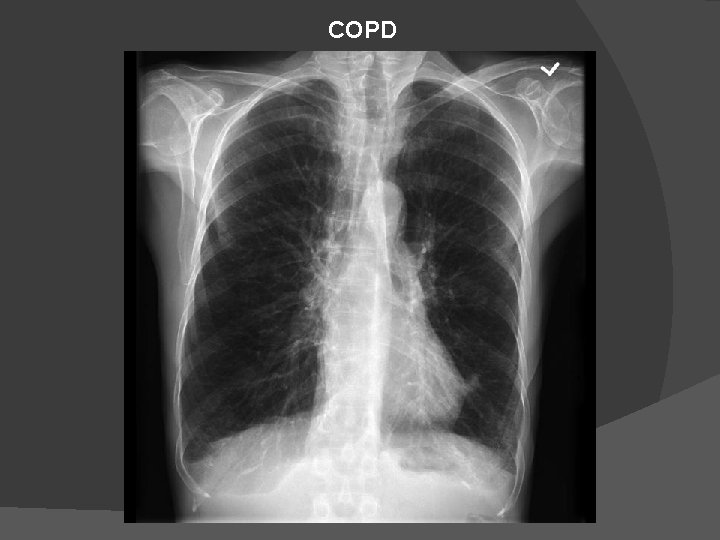

COPD